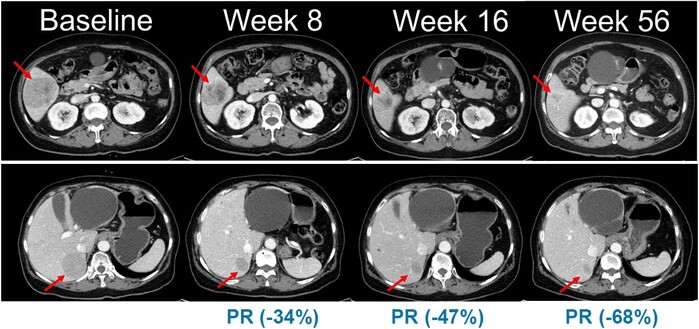

흑색종은 재발 위험이 높고 치료 옵션이 제한적인 난치성 피부암으로, 현재 사용되는 주요 치료제 대부분이 해외 제약사 제품에 의존하고 있다. 이 가운데 벨바라페닙은 치료목적사용 승인을 통해 일부 환자에게 제한적으로 투약되며 항종양 효과 가능성을 확인해 왔다.

벨바라페닙은 종양 세포 성장에 핵심적인 MAPK 신호전달 경로 중 RAF 및 RAS 유전자 돌연변이를 표적으로 억제하는 경구용 항암제다. 기존 BRAF 저해제가 단일체(monomer)를 중심으로 작용하는 것과 달리, 벨바라페닙은 BRAF 및 CRAF 이합체(dimer)를 선택적으로 저해하도록 설계돼 RAF 이합체 형성에 따른 내성 문제를 극복할 수 있는 차별화된 기전을 갖는다.

이와 함께 MEK 억제제와 병용할 경우 MAPK 경로를 보다 효과적으로 차단해 기존 치료의 한계를 보완하고, BRAF ClassⅡ/Ⅲ 변이 및 RAS 변이를 포함한 폭넓은 환자군에서 치료 효과를 기대할 수 있는 전략으로 평가된다.